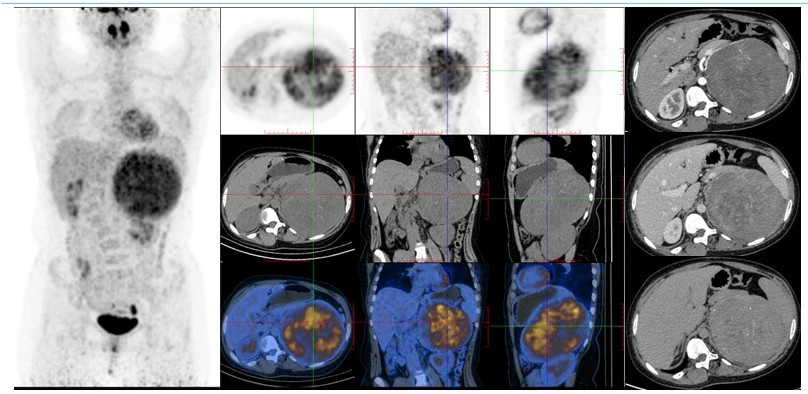

病例(2为一老年男性,因发热伴间断性后背部坠胀、疼痛不适就诊;增强CT腹膜后巨大占位,平扫呈混杂稍低密度,其内部及边缘见点状钙化少许脂肪密度,增强扫描呈不均匀强化;18F-FDG PET/CT示占位代谢轻度不均匀增高;(右侧腹膜后肿物)穿刺病理为脂肪肉瘤

病例2. 男,81岁,发热伴间断性后背部坠胀、疼痛不适脂肪肉瘤